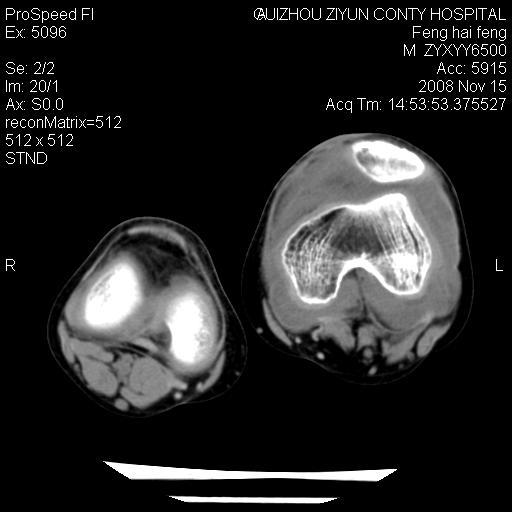

标题: CT16656:M 14Y 左膝关节肿胀一年余。其余病史不详。 [打印本页]

标题: CT16656:M 14Y 左膝关节肿胀一年余。其余病史不详。

考虑左侧髌骨结核;左膝关节滑膜肿胀、增厚,关节囊积液。

左膝滑膜型关节结核可能性大!支持!滑膜型关节结核主要ct表现:关节囊肿胀,积液,关节面见小破坏灶,并见点状死骨!

左膝滑膜型关节结核可能性大!支持!滑膜型关节结核主要ct表现:关节囊肿胀,积液,关节面见小破坏灶,并见点状死骨

好大的左腿!考虑左侧髌骨结核,左膝关节滑膜肿胀、增厚,关节囊积液。

左侧髌骨结核;左膝关节滑膜肿胀、增厚,关节囊积液